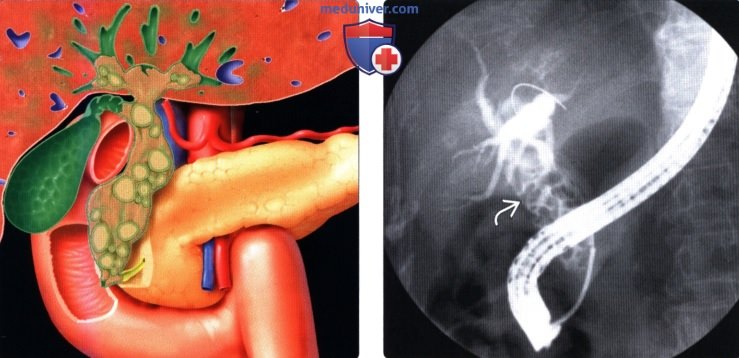

Фотографии и изображения, связанные с симптомами первичного склерозирующего холангита